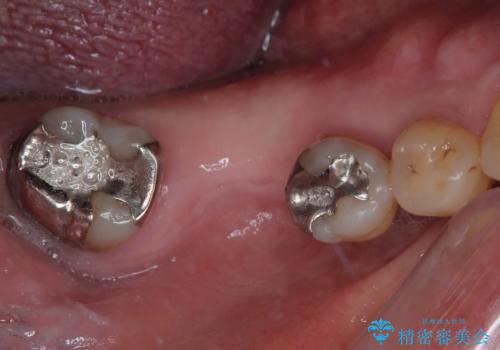

割れて揺れている奥歯 抜歯即時・早期埋入インプラント治療